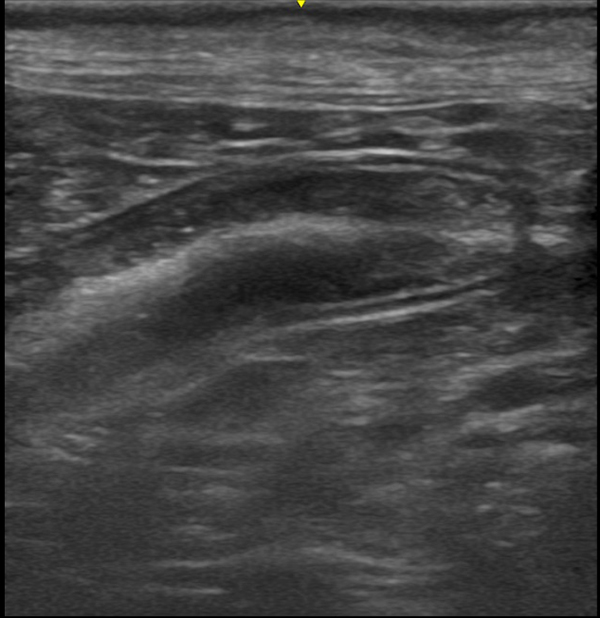

• 超音波検査

膵炎の診断には血液検査や超音波検査などが重要な役割を果たします。

当院では膵炎を疑う症状を認めた場合は、これらの検査を実施し、膵臓や周囲の臓器の状態を詳しく評価します。

超音波検査や内視鏡検査を組み合わせ、細胞や組織を採取することで消化器型リンパ腫の診断が可能です。